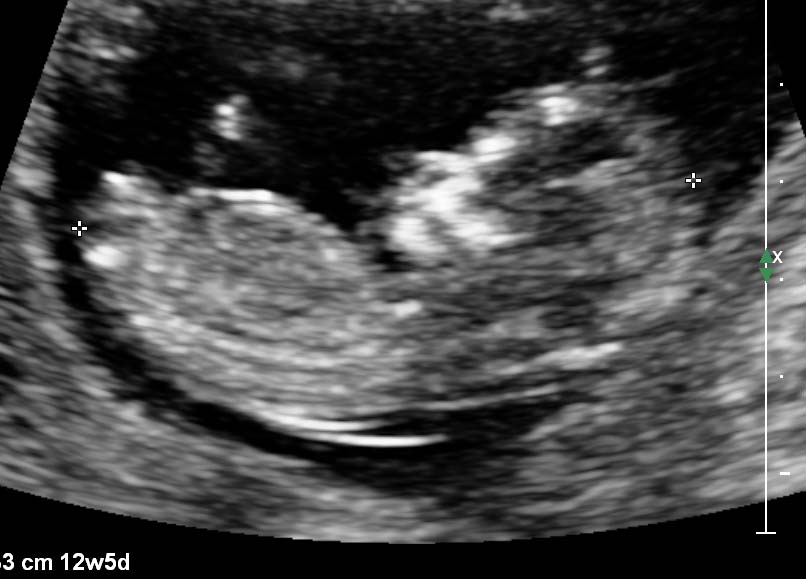

I am as curious as everyone else is with their beautiful scans. I have done a somewhat lazy sway after a miscarriage in October last year. I am of course over the moon with making it this far, but would love to know your guesses....PLEASE:):flowerz:Attachment 9063Attachment 9064